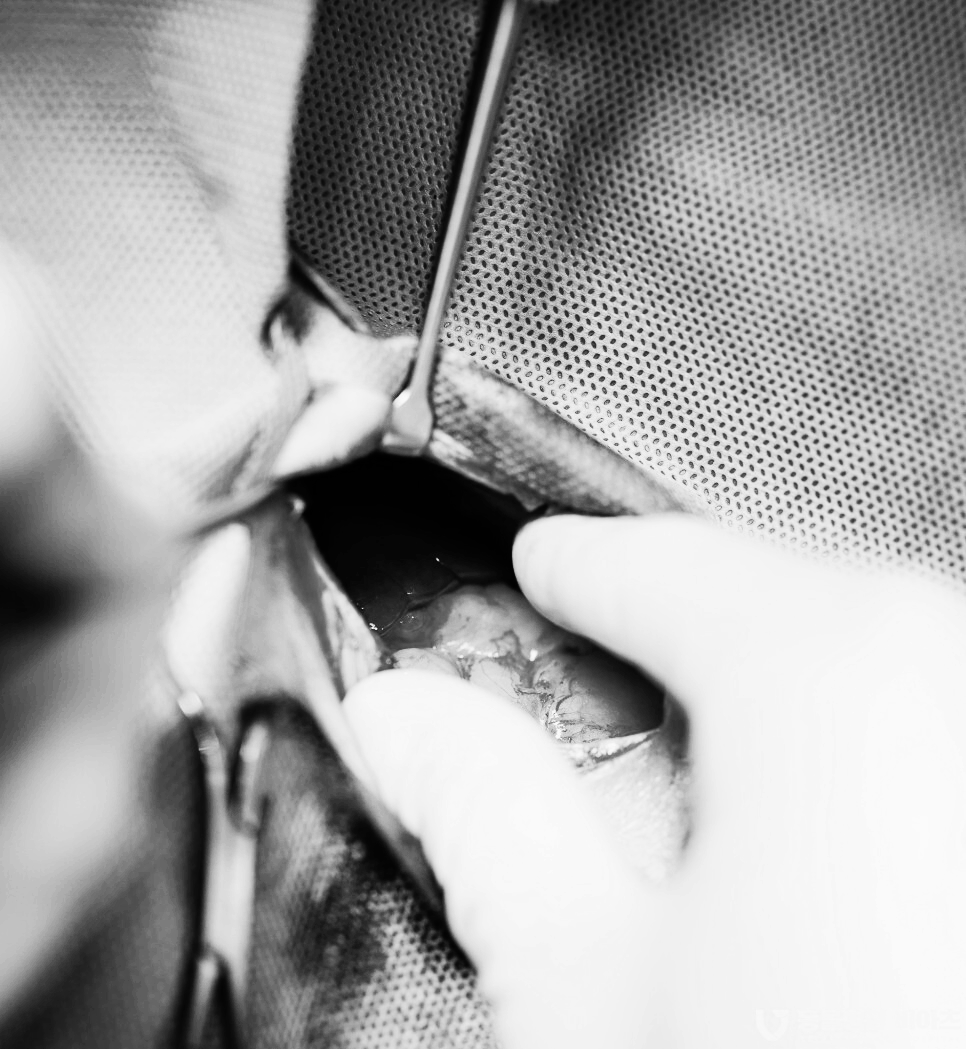

완벽히 살균된 수술 도구가 들어옵니다.

언제 봐도 차갑고 무시무시한 도구입니다.

수술 부위 털을 제거합니다.

경험이 풍부한 원장님의 집도하에

능숙하게 수술이 진행됩니다.

다음 사진들은 비위가 약한 분들은 보지 마셔요